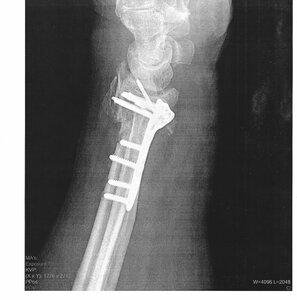

I had an accident up snowboarding yesterday. By the time I got home my ankle was swelling fast. the wife ran me down to the ortho clinic and sure enough i broke my leg - maybe in two places - on break is certain. Booted now, surgery Wednesday. getting some new titanium implants put in to hold everything it the right places. I think the doc said no weight bearing for at least 6 weeks. gonna miss wo month of the season, cooking is almost out of the question.

In an odd twist of fate - I had the same break on the same leg about 25 years ago. that one was much worse, it was super displaced and almost a compound fracture. spend 4 days in the hospital that time. this one is out patient and Im hoping they have better methods. the first surgery was the most pain i have ever felt.

I was having fun when I broke my right tib/fib back in '04.

Xray%20plates%20and%20screws%202002.jpg